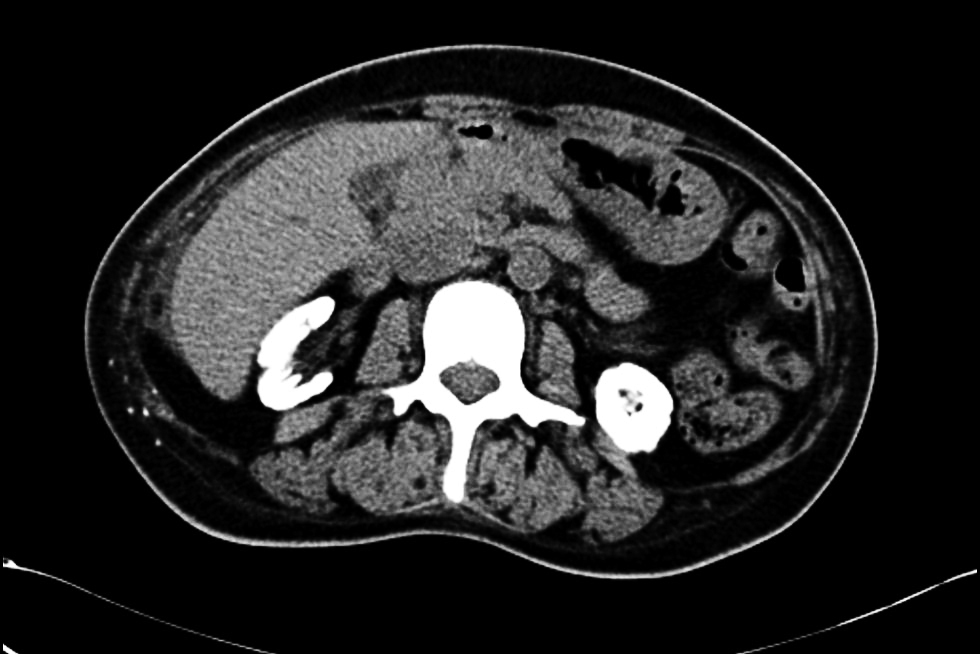

辅助检查:心电图检查示窦性心律,室性早搏。血管彩超见右上肢动脉中内膜点状钙化斑形成,左上肢动静脉内瘘血管中内膜点状钙化斑形成(图1)。双下肢和双手X线检查:双手诸骨骨质密度不均匀增高,部分远节指骨骨质吸收(图2),右手指骨周围见血管钙化影和结节状高密度影,诸小关节在位,关节间隙尚可,周围软组织未见明显肿胀;双髋关节在位,髋关节间隙变窄,双侧股骨骨质密度增高。双膝、双踝关节,双足诸小关节在位,关节间隙尚可,双膝、双踝、双足关节面下骨质密度不均匀增高(图2)。心脏彩超检查:双心房扩大,二尖瓣环钙化,二尖瓣轻度反流,三尖瓣轻-中度反流和卵圆孔未闭(房水平左向右分流)。胸腹部计算机体层成像(CT)平扫:(1)双肾萎缩钙化;(2)全身广泛骨质密度增高;(3)脾脏饱满,动脉粥样硬化。与2021年5月21日胸部X线片比较,胸廓诸骨骨质密度增高稍有进展(图3)。骨髓涂片检查:骨髓细胞增生减低,中性粒细胞系占68.0%,以分叶核细胞为主,嗜酸细胞可见;红细胞系占1.2%,成熟红细胞大小不均,部分细胞中心淡染区扩大;淋巴细胞比例增高;未见巨核细胞,血小板散在。骨髓病理检查结果:骨髓部分组织破碎,伴纤维组织增生,增生程度无法明确判断,骨髓小梁结构紊乱伴髓腔变形,部分小梁硬化,髓腔内见多量结晶样物沉积,有少量偏成熟粒细胞散在分布,未见红系和巨核系(图4A),偏振光镜下可见特征性双折射(图4B)。

本例PH患者接受维持性血液透析治疗4年,除肾脏受累外,还伴有多系统病变,总结如下。(1)重度顽固性贫血:患者乏力明显,精神萎靡,贫血貌,在外院反复接受输血治疗,且在使用较大剂量罗沙司他情况下,血红蛋白仍波动在65 g/L左右。患者粪便潜血阴性,可排除消化道出血,结合病史、骨髓活检以及硫代硫酸钠经验性治疗效果,证实草酸盐结晶骨髓沉积是骨髓造血受损的主要病因。既往也有文献报道重度顽固性贫血是PH患者特征性表现之一。需要注意的是,本例患者以贫血为主要表现,白细胞和血小板计数正常,这与既往报道的全血细胞减少存在差异[5, 6]。经文献检索发现,本例患者骨髓组织草酸盐结晶的病理表现是目前已报道病例中最具有特征性改变的病例。(2)骨痛、骨关节畸形和骨质密度增高:患者主诉双手疼痛麻木,伴有双足跟疼痛,四肢关节活动受限。结合其胸腹部CT表现为全身广泛骨质密度增高,以及X线检查示双手诸骨骨质密度不均匀增高,部分远节指骨骨质吸收;髋关节间隙变窄;双侧股骨骨质密度增高;双膝、双踝、双足关节面下骨质密度不均匀增高,提示草酸盐沉积于骨导致骨钙化,而非一般性肾性骨病,后者常以骨质疏松、骨软化、纤维囊性骨炎及病理性骨折为特征。由于PH的罕见性和缺乏大样本的系统研究,PH骨损害的流行病学特征目前仍不清楚。值得注意的是,即使在未出现临床症状时,部分患者已出现明显骨损害影像学改变[7]。我们既往报告的1例PH 1型患者也是以骨质密度增高、骨组织破坏、骨结构紊乱,草酸钙沉积骨及骨周组织改变为临床特征[3],与本例相似。因此,早期的骨骼系统筛查可能对PH诊疗有着重要价值。(3)心脏病变:虽然目前尚无草酸盐沉积于心脏的直接证据,但本例患者血压较前显著降低,波动在80~83/54~50 mmHg,肌钙蛋白I升高;心脏彩超检查示双心房扩大、二尖瓣环钙化。心脏病变受到多种因素的影响,本例患者除考虑贫血外,还可能与草酸盐沉积于心脏组织有关。既往也有草酸盐沉积于心脏组织的文献报道[8]。(4)血管钙化:草酸盐沉积于血管是PH患者发生血管钙化的重要发病机制[9]。本例患者血管彩超结果示左右上肢动脉中内膜点状钙化斑形成;胸腹部CT亦可见较广泛血管钙化;X线检查示右手指骨周围见血管钙化影。目前,草酸盐沉积于血管的选择性仍不明确。研究显示,皮肤微血管功能障碍可作为PH 1型患者心血管损害的早期标志物[10],提示草酸盐较易沉积于微小血管。(5)低白蛋白血症:本例患者体重指数、血脂正常,透析充分性良好,自诉饮食合理,每次透析使用人血白蛋白10 g,但仍表现为顽固性低白蛋白血症,这与既往文献报道并不完全一致[11, 12],且与PH分型无关[13]。目前,PH患者发生低白蛋白血症的病因不清楚,考虑到PH是以肝脏特异性基因突变导致草酸盐产生过多为临床特征,肝脏基因突变间接引起的肝脏白蛋白合成异常可能是顽固性低白蛋白血症的原因。(6)高凝状态:本例患者平素使用大剂量抗凝药物。即使在高强度抗凝情况下,透析器中仍可见血栓形成。同时,近6个月来反复因动静脉内瘘血栓形成而导致动静脉内瘘功能不良,血D-二聚体多次较正常值升高10多倍,纤维蛋白(原)降解产物升高数倍,表明本例患者存在高凝状态和纤溶亢进。经文献检索发现,本例为PH合并高凝状态的首次报道,其发生机制仍不清楚,推测可能与转氨酶相关基因突变导致凝血因子和纤溶蛋白合成异常及草酸盐沉积引起内皮损伤有关[14]。既往有个案报道显示,肝移植能够治愈合并血栓形成倾向的PH 1型患者[15]。